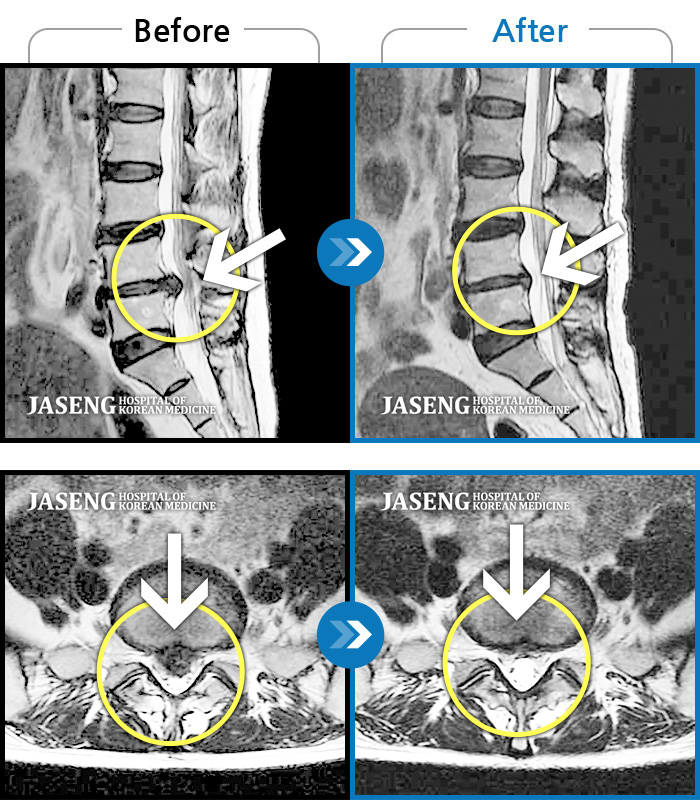

MRI사진에서 좋아지고 있다는 말씀에 넘 기뻤습니다^_^